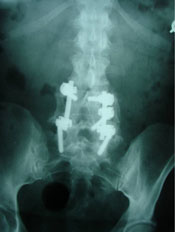

Probably no area of chiropractic spinal manipulation is as challenged as treating the post-surgical patient who is the same, worse, or disenchanted with their surgical outcome. Certainly, the opportunity to treat the patient before surgical intervention is best. When confronted with this post-surgical patient, however, the chiropractic physician proceeds as if with a patient who has not had surgery. i.e. The chiropractor will proceed with the careful history and clinical examination to determine what is causing the pain. That cause may be within the surgical site or adjacent to it. In treating the post-surgical spine, fusion or no fusion is a dictator of care. If there is a fusion, spinal manipulation is given to adjacent levels of the spine to the fused area. If there is no fusion, the doctor carefully proceeds as if no surgery. Some motion may be possible within the spine depending on the surgical procedure performed. (11)